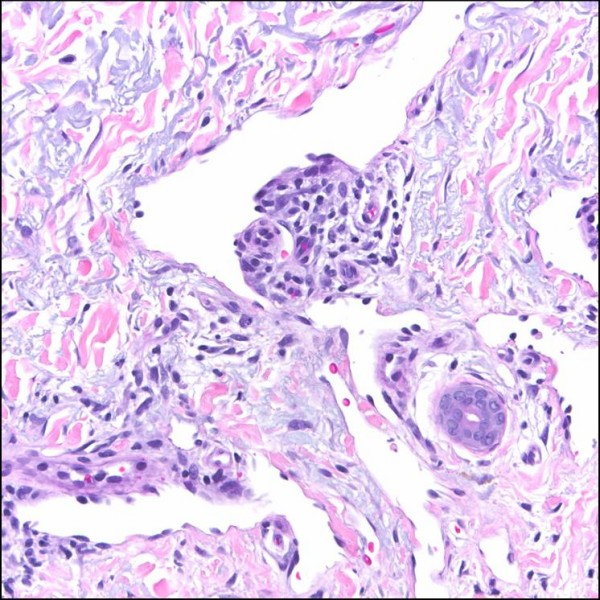

Figure A – Probably, you cannot see it, but this is a nervous tissue and it is not completely healthy. In the picture we can find a microglial which is changed after contact with HIV. This transformed microglial we call multinucleated cells. That kind of pictures is typical for encephalopathy caused by HIV. Microglia comes from mesoderm and its function is analogous to leukocytes. This is a very special population of cells in CNS because only microglia do not come from neuroepithelium. License: CC0